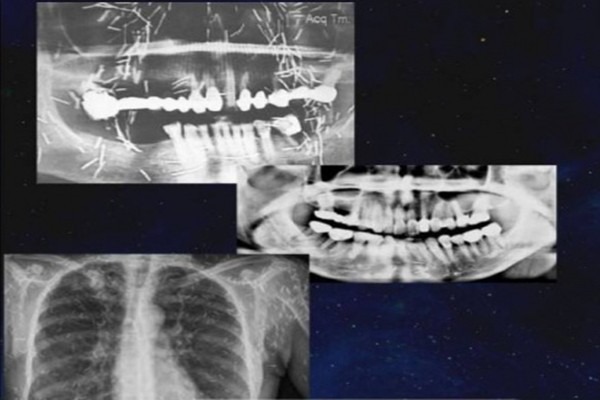

Châm cứu trong y học cổ truyền Trung Quốc là phương pháp sử dụng kim đặc chế để kích thích các huyệt đạo nhằm đạt được tác dụng giảm đau và chữa bệnh.

Tuy nhiên, một bác sĩ ở Malaysia chia sẻ, anh từng gặp một nữ bệnh nhân bị đột quỵ, liệt và không thể nói được. Sau nhiều lần kiểm tra, bác sĩ phát hiện ra số lượng lớn "kim bùa" (hay còn gọi là kim quyến rũ) được cấy vào cơ thể người phụ nữ, bao gồm cả mặt, cổ và ngực. Thế nhưng khi bị phát hiện, người phụ nữ vẫn không chịu lấy kim ra, cuối cùng tử vong.

Theo bác sĩ Razif, khi còn làm việc tại bệnh viện ở Kedah, anh gặp một người phụ nữ khoảng 60 tuổi nhập viện do đột quỵ, bị liệt một bên cơ thể, không nói được nhưng vẫn tỉnh táo và phản ứng nhanh khi được gọi.

"Tôi không biết điều gì đã đầu độc tâm trí cô ấy. Các con cô ấy chắc chắn không biết chuyện này nhưng vì quy định của bệnh viện tôn trọng ý muốn của bệnh nhân, tôi không thể nói với các con cô ấy bất cứ điều gì. Tôi rất hy vọng bệnh nhân sẽ đồng ý loại bỏ hết số kim tích tụ trong người nhưng cô ấy không đồng ý. Sau khi bệnh nhân tử vong, tôi hối hận vì đã không nói cho con của bệnh nhân biết tường tận sự việc", bác sĩ Razif nói.

Theo tìm hiểu, ở Malaysia, thứ gọi là kim bùa có tên chính thức là Susuk hay kim quyến rũ, là những chiếc kim làm bằng vàng hoặc kim loại quý khác, được cắm vào các mô mềm của cơ thể để hoạt động như những lá bùa. Susuk có nhiều mục đích khác nhau, từ thẩm mỹ thuần túy đến điều trị đau khớp và các bệnh nhỏ khác.

Về vấn đề này, nhiều bác sĩ đã để lại bình luận, cho biết họ đã từng gặp những trường hợp như vậy, phần lớn là phụ nữ, không chỉ cấy kim vào mặt mà những người này còn cấy vào chân, bụng.